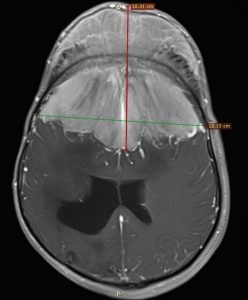

Мозъчен тумор с тегло над 1 килограм отстраниха в столичната болница "Св. Иван Рилски" в уникална операция, продължила осем часа, разказаха днес от екипа - д-р Емануил Найденов - неврохирург, доц. Станимир Сираков – неврорентгенолог, д-р Марин Пенков – неврорентгенолог и д-р Любомир Падарски – анестезиолог.

Божидар от години страдал от главоболие. Преди две години то станало непоносимо, зрението му драстично намаляло, а главата му видимо се деформирала. Въпреки това диагнозата не е поставена веднага, ходил е на очни лекари, но не е бил насочен за скенер за евентуален тумор дълго. Когато все пак това става, се оказва, че човекът има менингиом с огромни размери и лекарите, с които се консултира у нас и в чужбина, смятат, че болестта е в твърде напреднал стадий и рисковете от хирургичното лечение са огромни.

Избран е нов подход, за да се ограничи кръвозагубата при операцията. Първоначално лекарите извършват селективно запушване на голяма част от хранещите съдове на тумора, под високотехнологичен рентгенов и термографски контрол. „Основното предизвикателство беше големината на тумора и неговата анатомична форма. Ако се маха целият тумор, кръвозагубата би била несъвместима с живота. Затова направихме емболизация на лезията, с която запушихме повечето съдове, които я захранват с кръв“, обясни доц. Сираков, който е извършил първата част от интервенцията.